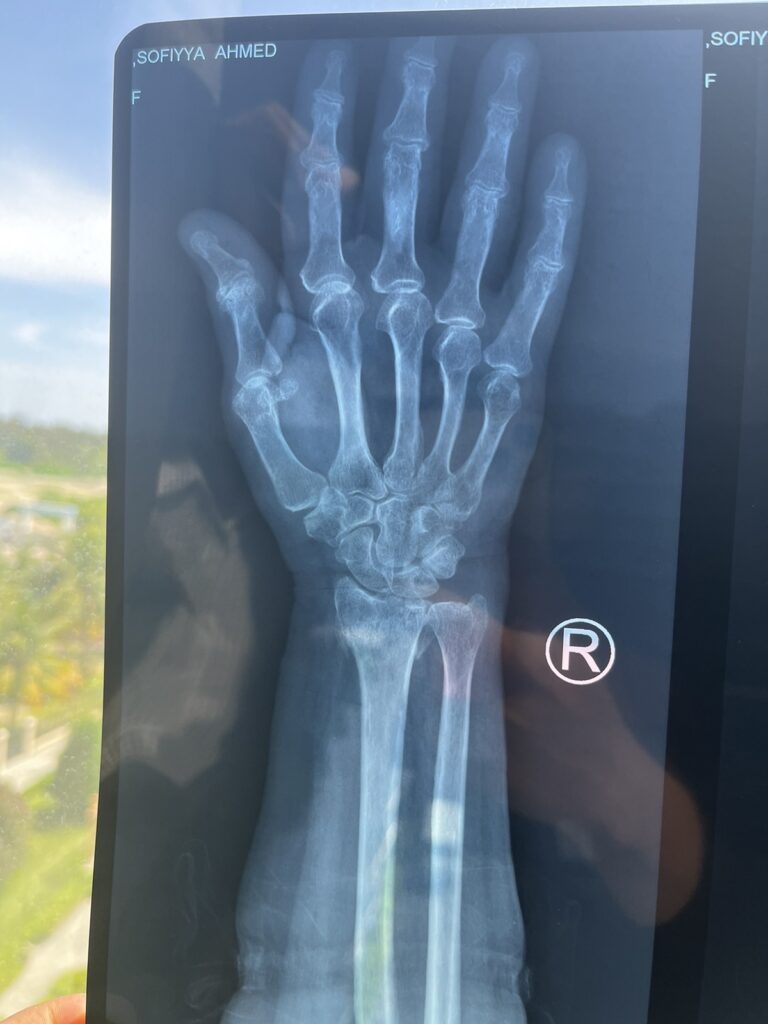

އެމްޓީސީސީ ބަހަކުން ސައިކަލެއްގައި ޖެހި އިއްޔެ ހިނގި އެކްސިޑެންޓްގައި އަނިޔާވި އުމުރުން ދުވަސްވީ އަންހެންމީހާގެ އަތުގެ ދެ ތަނަކުން ބިންދައިގެން ގޮސް މިއަދު އޮޕަރޭޝަން ކުރާނެ ކަމަށް އާއިލާއިން ބުނެފިއެވެ.